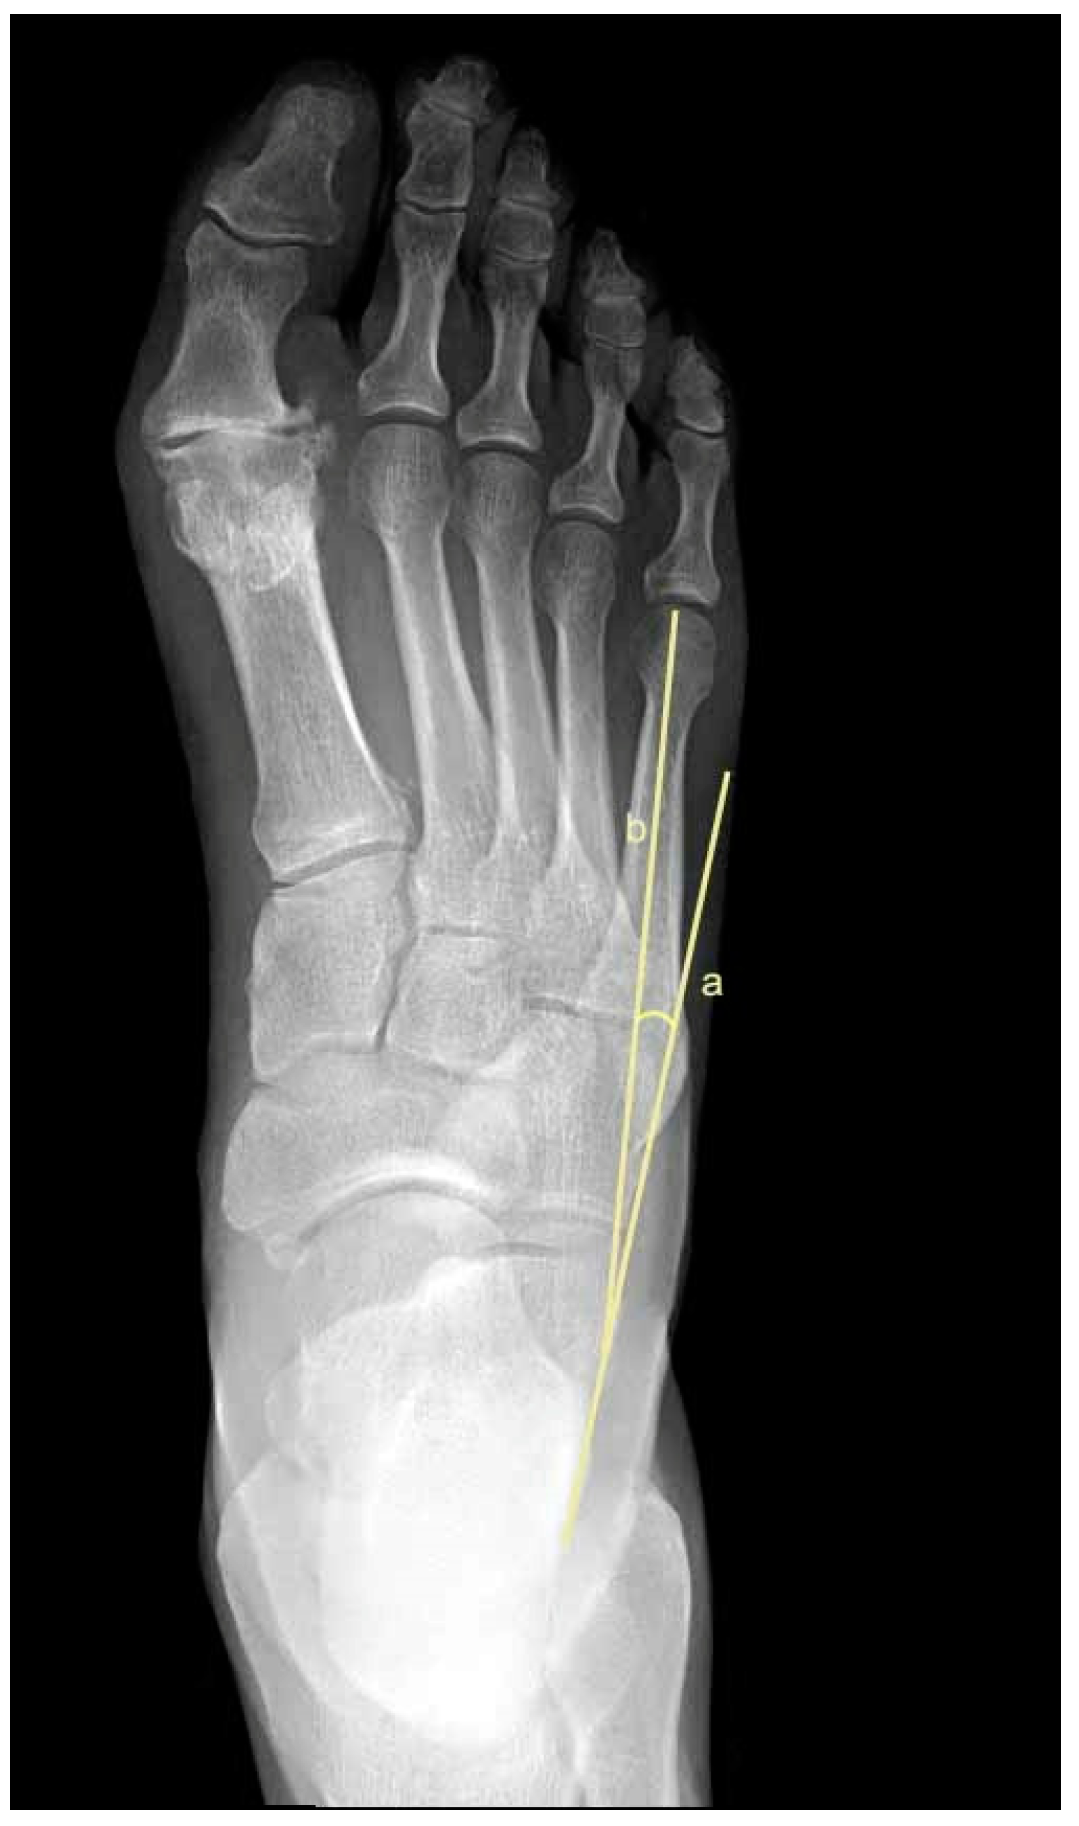

2.5. Metatarsus Adductus Measurements

- Sgarlato, T.E. Compendium of Podiatric Biomechanics; California College of Podiatric Medicine: San Francisco, CA, USA, 1971. [Google Scholar]

- Weissman, S.D. (Ed.) Biomechanically acquired foot types. In Radiology of the Foot; Williams and Wilkens: Baltimore, MD, USA, 1989. [Google Scholar]

- Gentili, A.; Masih, S.; Yao, L.; Seeger, L.L. Pictorial review: Foot axes and angles. Br. J. Radiol. 1996, 69, 968–974. [Google Scholar] [CrossRef]

- Ganley, J.V.; Ganley, T.J. Metatarsus adductus deformity. In Comprehensive Textbook of Foot Surgery, 2nd ed.; Wilkins, W., Ed.; Williams and Wilkens: Baltimore, MD, USA, 1992; pp. 829–852. [Google Scholar]

- Engel, E.; Erlick, N.; Krems, I. A simplified metatarsus adductus angle. J. Am. Podiatry Assoc. 1983, 73, 620–628. [Google Scholar]

- Kilmartin, T.E.; Flintham, C. Hallux valgus surgery: A simple method for evaluating the first-second intermetatarsal angle in the presence of metatarsus adductus. J. Foot Ankle Surg. 2003, 42, 165–166. [Google Scholar] [CrossRef]

- Dawoodi, A.I.S.; Perera, A. Radiological assessment of metatarsus adductus. Foot Ankle Surg. 2012, 18, 1–8. [Google Scholar] [CrossRef]